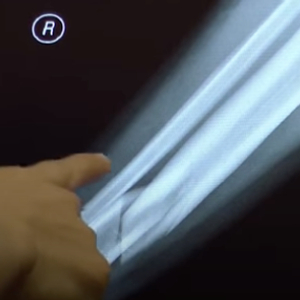

“断骨增高术”的原理,是先通过外科手术在骨骺线处打开,安装一个外固定器,每天调整这个外固定器刺激软骨细胞再生,让骨骼再次生长,达到一定高度后,再做一个二次手术将固定器取出来,让身高固定。

然而,北医三院一位骨科学主治医生王大夫对记者表示:骨头被拉断后,“人体的血管、神经还是连着的,如果为了增高而去打断原本健康的骨头,使骨头被迫不断延长,血管、神经生长可能跟不上,便可能出现骨头愈合不良或畸形愈合等问题。而且,人体下肢的力线被改变后,长期来看骨关节炎等并发症的发生率会明显增高。”